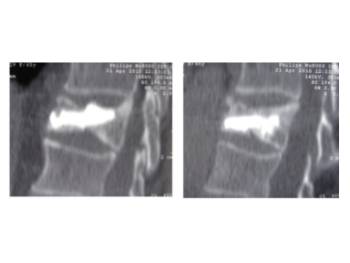

Pre- and post-operative comparison of a cemented kyphoplasty

Female, age 55, compression fracture of L2

Before 2

after 2